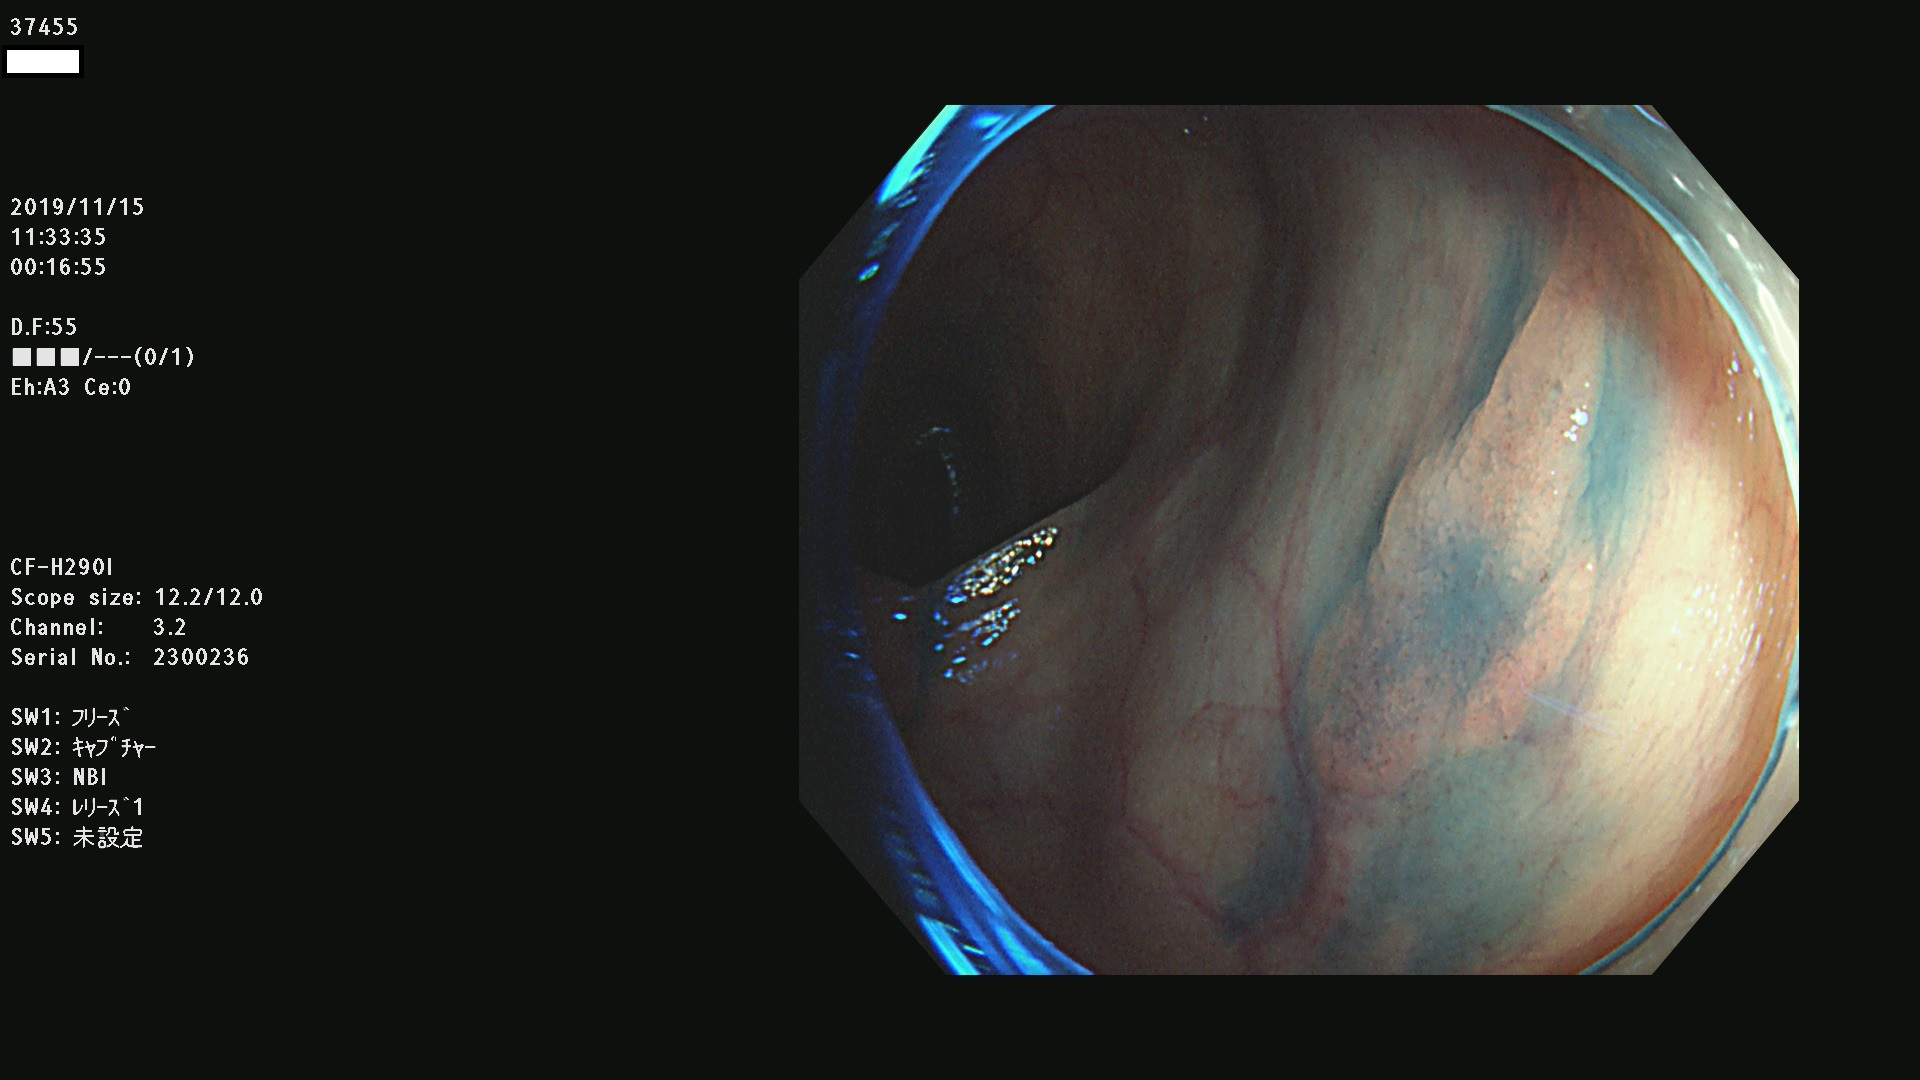

37400(SSAPのみ) 37401 37403 37404 37405 37406 37407 37408 37410 37411 37412 37413 37415 37416 37417 37420 37423 37424 37425 37426 37428 37430(SSAPのみ) 37432 37433 37434 37435 37436 37437 37438 37439 37440 37442 37443 37444 37447 37448 37449 37450 37451 37452 37455 37456 37457 37458 37459 37460 37461 37462 37464 37467 37468 37469 37470(SSAPのみ) 37471 37472 37474 37476(SSAPのみ) 37477 37478 37480 37481 37482 37483 37485 37486 37487 37488 37489 37490 37491 37492 37493 37494 37497 37499

発見困難で危険性の高い平坦型病変(上記100名より抽出)